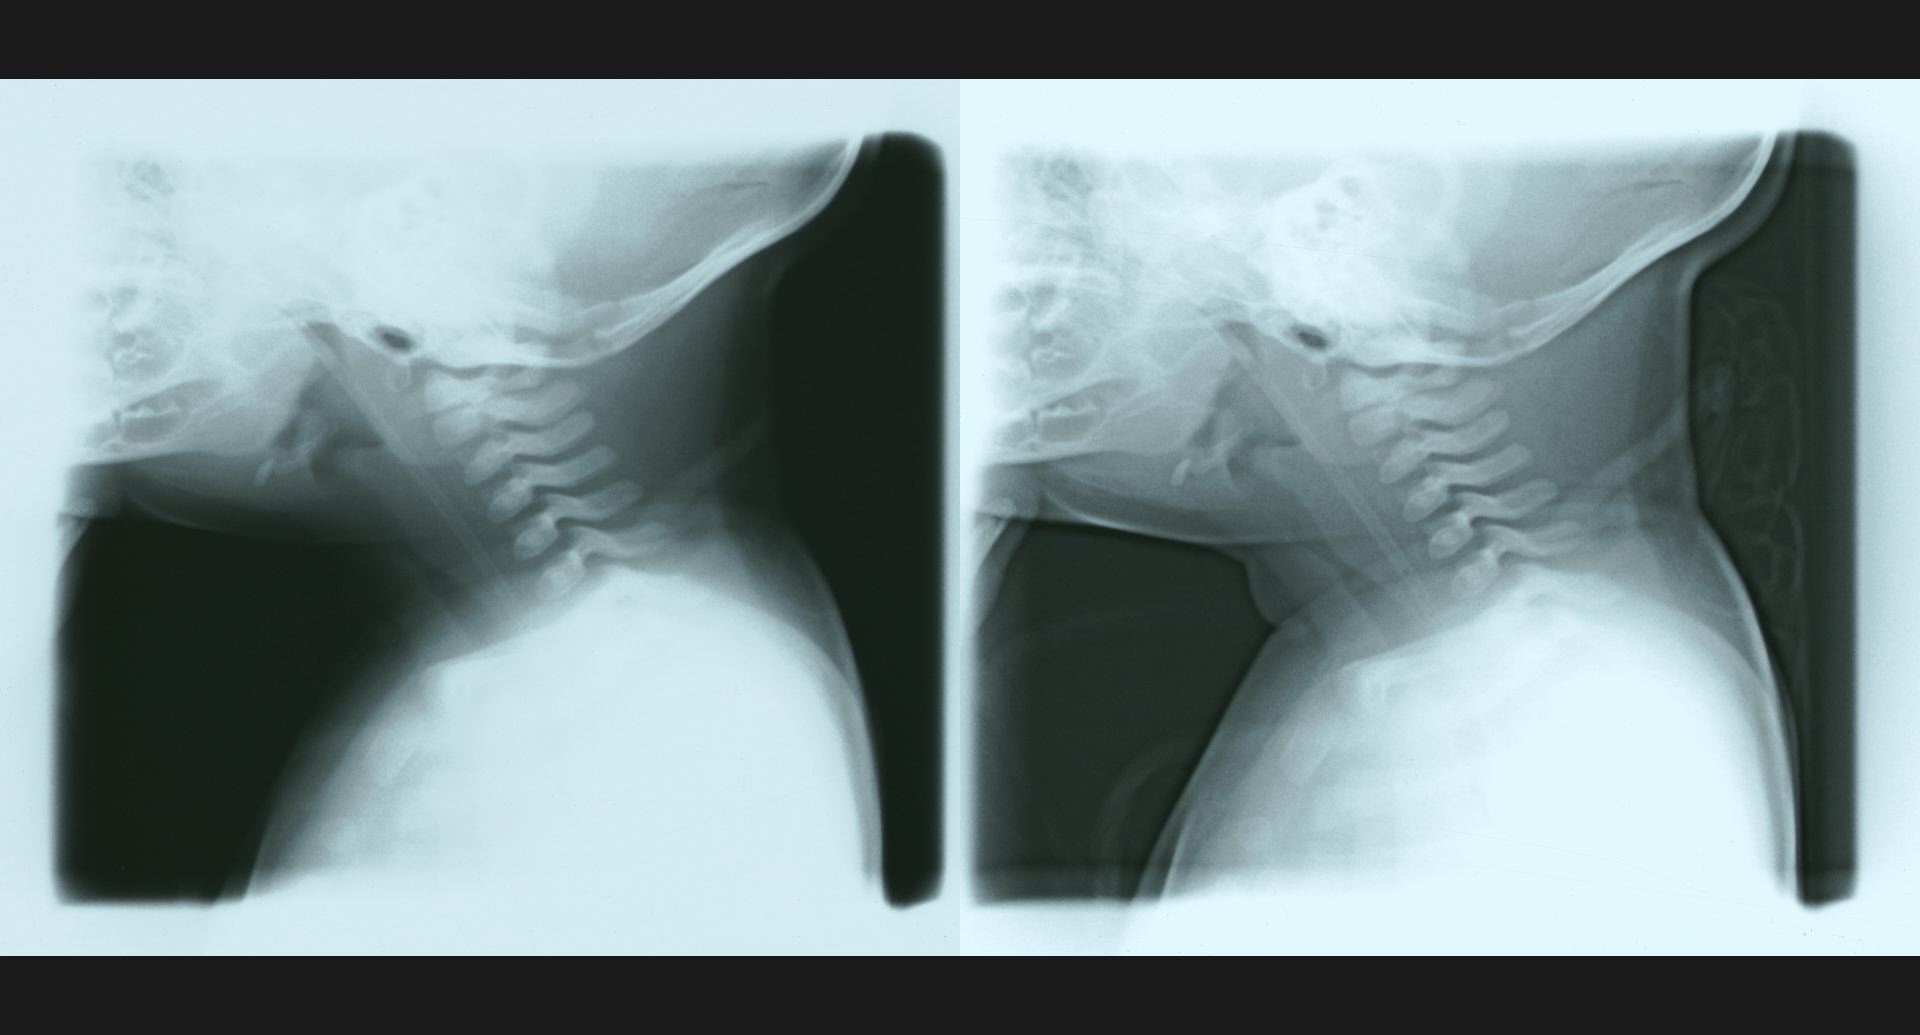

fig.14(77KB) :Phantom disc

disc内の透亮像。spur。